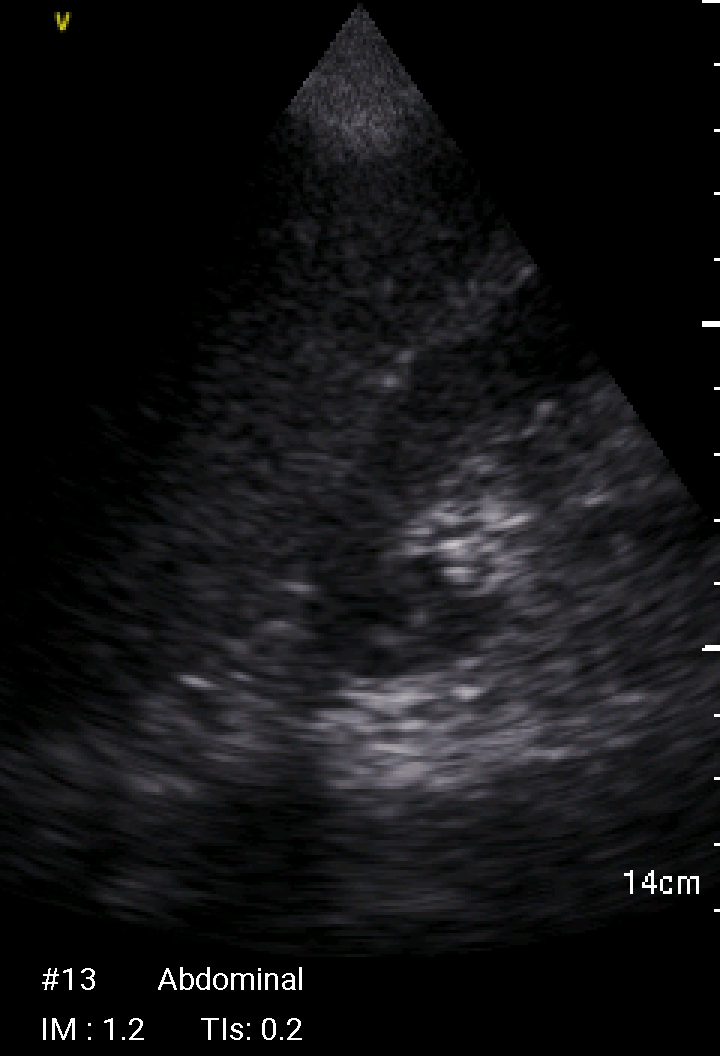

Echographie Sous-clavièreJugulaireFémorale JUGULAIRE G FEMORALE Dt MorissonKohlerDouglas Sous-clavièrePleural J’aime chargement…